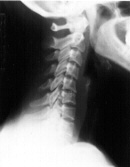

Few if any headache sufferers have a normal neck.  Many have excessive muscular tension alone but the vast majority have a loss of normal spine posture.  In the spine the neck has a natural forward curve of about 40 degrees.  This insures proper balance of the head on the torso.  But through injury, poor posture or birth defect the forward curve can become lost.  This loss can even result from forceps delivery or birth trauma.  Loss of the forward curve mean excess strain to the neck muscles and meninges and a lifetime of headaches can result.  Obviously no medication will change posture or mechanical irritation of the neck.

Abnormal Curve